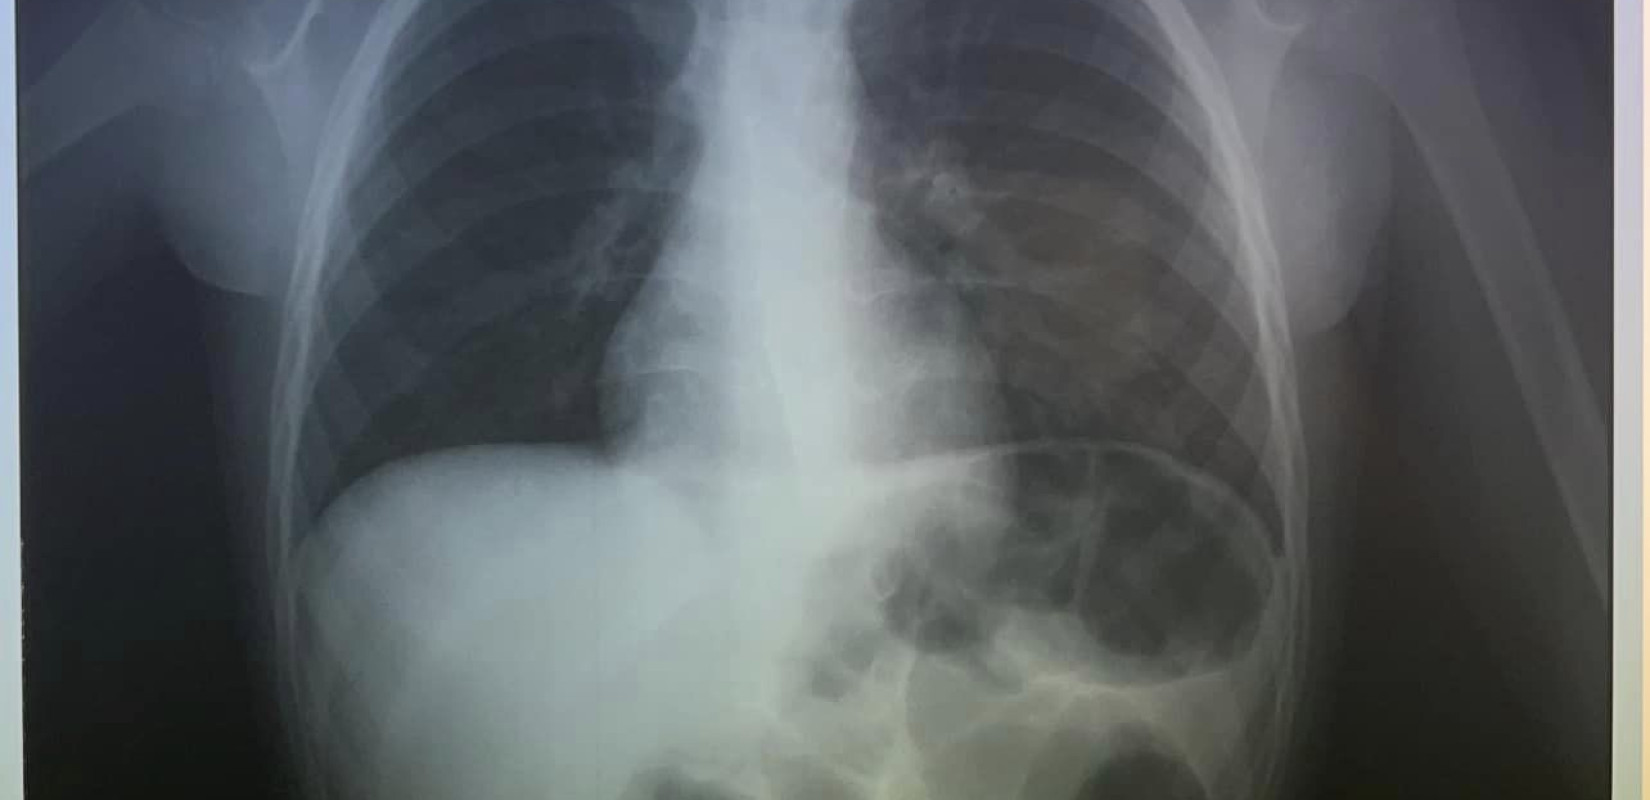

Σύμφωνα με το cretapost, το 4χρονο παιδί είχε καταπιεί ένα κέρμα και δεν μπορούσε να αναπνεύσει.

Άμεσα οδηγήθηκε στο ΠΑΓΝΗ με τους γιατρούς να προχωρούν σε επείγουσα αφαίρεση η οποία στέφθηκε με επιτυχία.